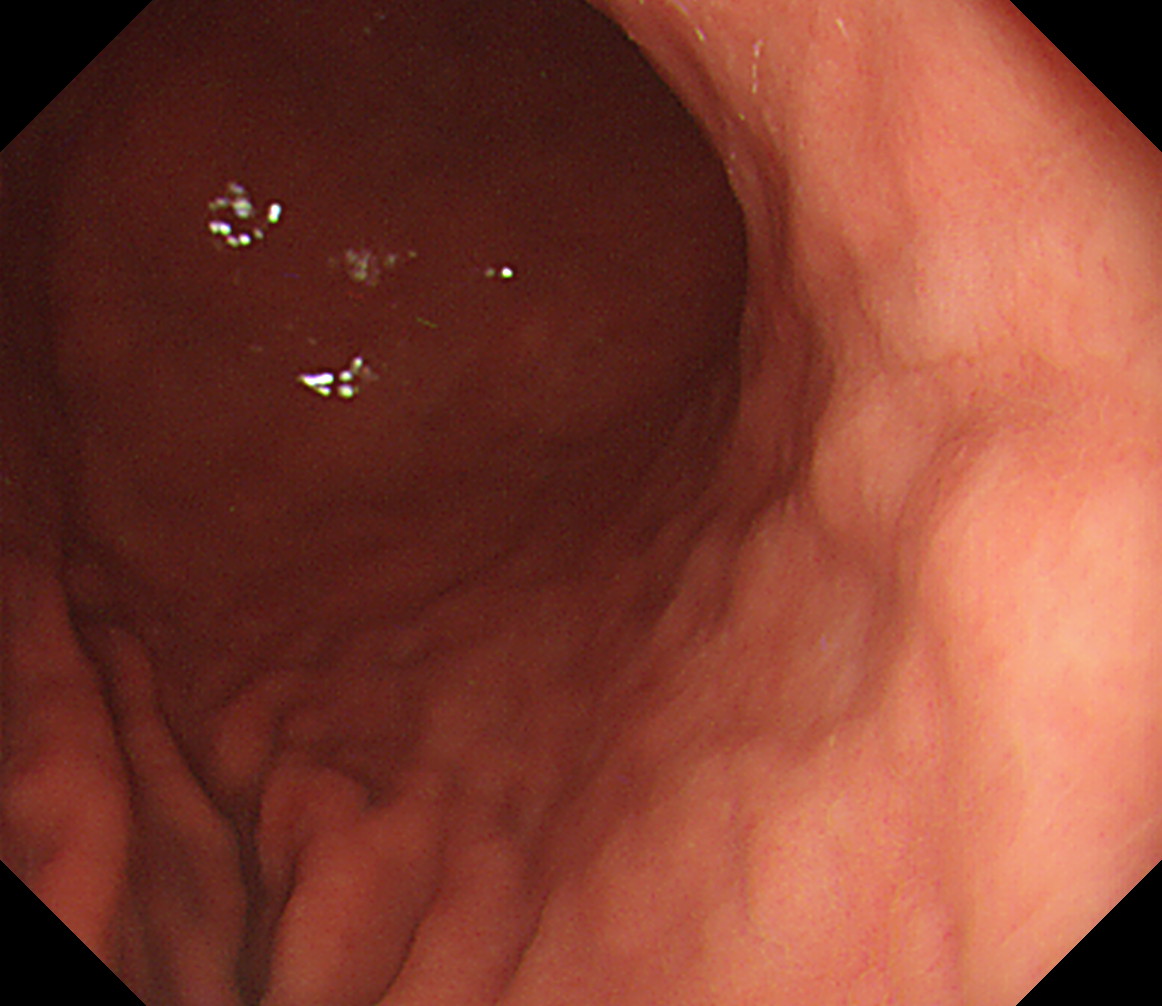

32 体上部後壁(分水嶺) 分水嶺は胃体上部と穹窿部の境界だが病変の多い部分なのでこの画面に分水嶺全体を入れる

後壁から反時計回り

噴門部小弯[J反転]

33 体上部小弯 胃角部大弯

34 体上部前壁 接線になり見逃しやすい部位です 体下部後壁

35 体上部大弯 エアーを十分入れて襞の間の病変を見逃さないようにする 体下部小弯